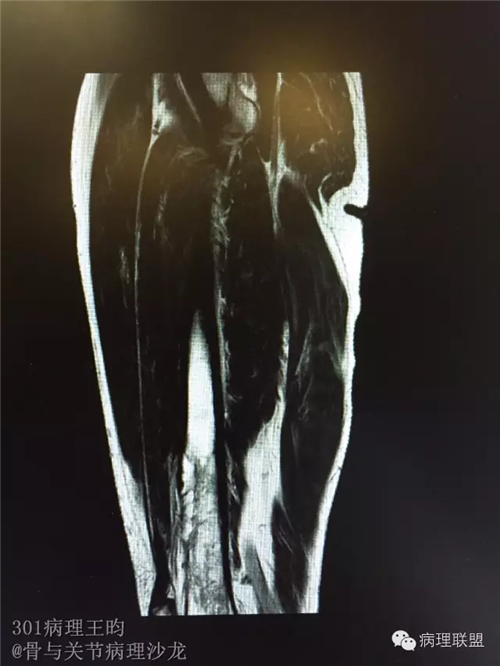

右股骨髓内高分化低级别骨肉瘤or骨纤维异常增殖症(Fibrous Dysplasia)?

男,36岁,活动后疼痛,发现右股骨远端肿瘤。